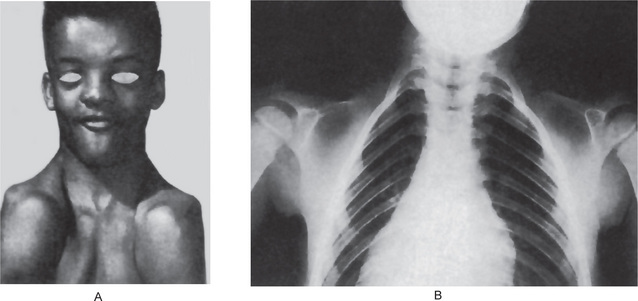

The bones in patients with osteogenesis imperfecta exhibit thin cortices, sometimes being composed of immature spongy bone, while the trabeculae of the cancellous bone are delicate and often show microfractures (Fig. 17-1). Osteoblastic activity appears retarded and imperfect, and for this reason the thickness of the long bones is deficient. The basic defect appears to lie in the organic matrix with failure of fetal collagen to be transformed into mature collagen. Qualitative defects (abnormal collagen I molecule) and quantitative defects (decrease in production of normal collagen I molecules) both exist. There is some evidence that the progressive intermolecular cross-linkage of adjacent collagen molecules, which is an essential characteristic of normal collagen maturation, is defective in this disease. Calcification proceeds normally. Defective microvascular system and decreased collagen fibril diameter have also been observed. The length of the long bones is usually normal unless multiple fractures have caused undue shortening.

Figure 17-1 Osteogenesis imperfecta (OI).

The typical microscopic changes of OI can be seen in a section of a long bone of a severely affected child. The bone cortex is thin and porous. The bone trabeculae are thin, delicate, and widely separated. Many osteoblasts and osteocytes are present, but the formation and organization of osteoid is deficient. There is less bone tissue than normal and most of it is woven or nonlamellar bone with collagen fibers of small size and random distribution. The woven bone has an increase in basophilic ground substance (shown by blue staining in H and E sections). (Courtesy of Dr Robert C Mellors)